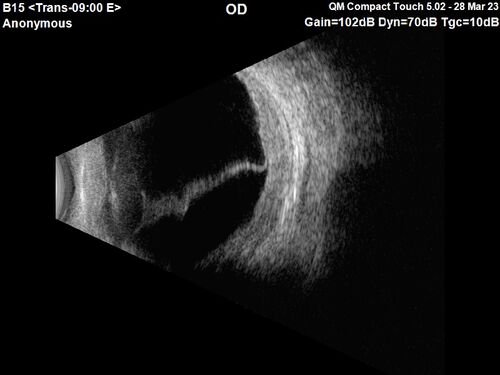

Choroidal Metastatic Breast Cancer with Exudative Detachment

58 year old female presented with 20/200 vision. Had 10 sessions of radiation and tumor shrank. The exudative detachment took almost a year to resolve. The vision improved to 20/40.